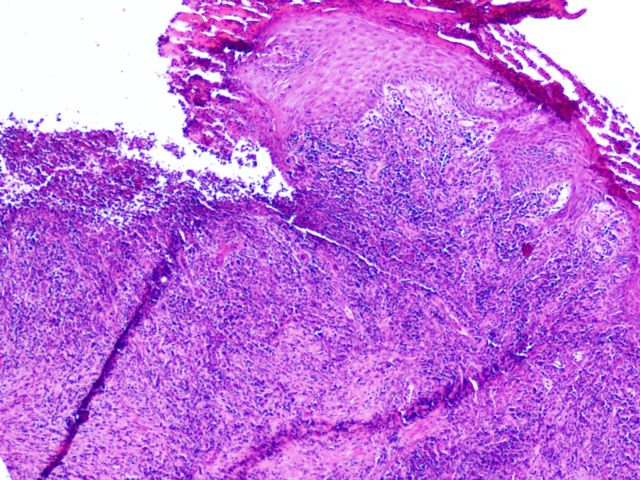

346 -- pa220052.jpg